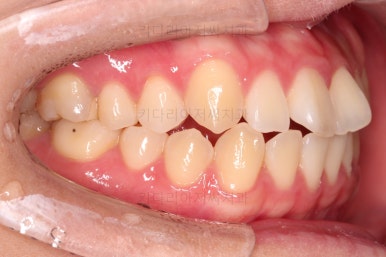

1. 처음 내원 시의 입안의 모습

부산치아교정잘하는곳 키다리아저씨치과에 처음 내원하셨을 당시의 입안 모습입니다.

얼핏 보면 많이 삐뚤어지지는 않은 편인데, 눈에 바로 띄는 앞니가 뻗쳐 있으면서 획 돌아있는데요. 정렬이 필요한 상황이었습니다.

어금니쪽은 많이 삐뚠 편은 아니었으며, 윗니 앞니가 많이 앞으로 뻗쳐 있는 상태였습니다.